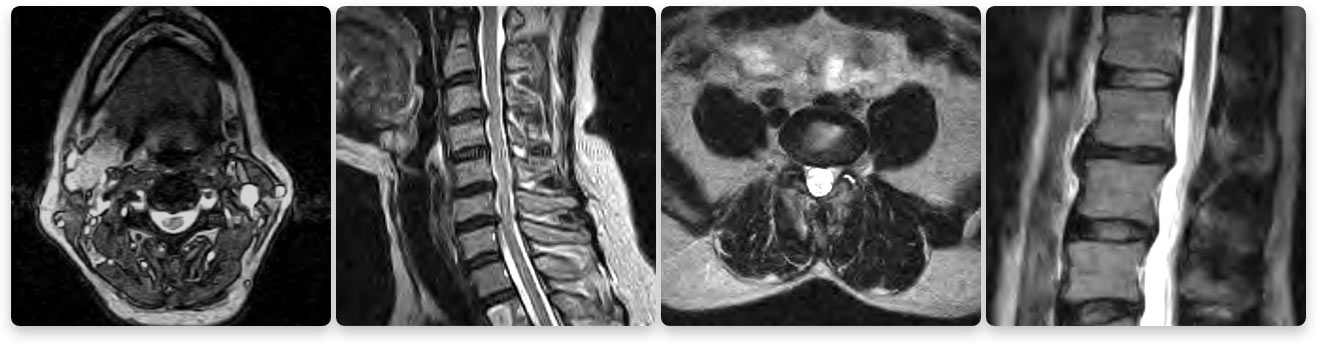

Texas Health Southlake's Imaging Department's 1.5T High Definition MRI Images

Seeing is believing. Do not compromise quality for a lower price. The images above compare a low strength machine to our 1.5T high-field machine. Two of the biggest factors that contribute to MRI image quality are strength of the magnet and skill of the technologist.

- 1.5T is the gold standard for a MRI in a clinical setting. DO NOT settle for less.

Beware of MRIs with lower magnet or tesla strength (Tesla is a measurement of magnetic field strength). The gold standard of MRI today is a 1.5T (T stands for tesla) strength MRI because it produces extremely clear images for a very accurate diagnosis. A lower-strength MRI produces images where the quality is much lower. You want to take care that you are not compromising your diagnosis when choosing an MRI.

1.5 tesla indicates the field-strength of the magnet used to obtain the images – the higher the field-strength, the more clear or detailed the images. A radiologist is looking to obtain the highest level of clarity for the most accurate diagnosis. Think of a spine injury. Let’s use, for example, a bulging disk. An MRI will show the anatomy of the vertebrae as well as the disks, spinal cord and the spaces between the vertebrae through which nerves pass. With such a complex image, your doctor will want the most clear, distinct picture so they can accurately assess the injury and make the proper diagnosis for treatment. The strength of the magnet is extremely important to achieve this clarity.

Lower strength means a less detailed image. The physician will have a harder time diagnosing the problem if he or she is looking at a low-quality image. These scans often take longer, making the patient more susceptible to movement resulting in reduced image quality. Lower image quality may lead to a longer wait time for the physician to read the scan or even misdiagnoses. Often prior to therapy, the entire scan may need to be redone. This costs you and your insurance company more money and may delay your diagnosis and treatment.

A true open MRI machine (one that is open on three sides) always has a tesla that is lower than 1.5. Patients sacrifice magnet power for a more open machine therefore they sacrifice image quality.